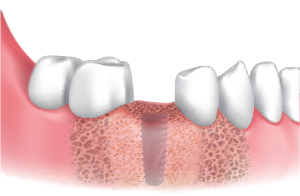

Caso clínico utilizando fresa de obtención Ø3.5/4.0.

Se realizó fresado a 300 RPM luego de marcar posición del sitio de implante y obtención.

La pantalla de silicona se llevó a contacto íntimo con los distintos niveles de hueso para prevenir la pérdida de limalla de hueso.

Luego de la instalación del implante, se conectan los pilares de cicatrización y se lleva a cabo la regeneración ósea en el defecto.